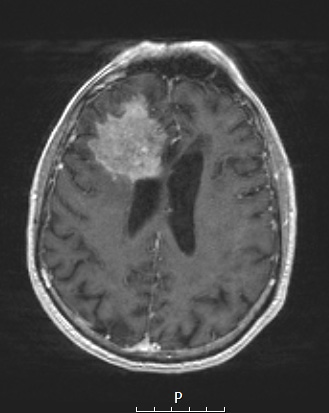

7A3 Amyloidoma (Case 7) T1W 2 - Copy

The T1-weighted exam enhances with contrast administration.